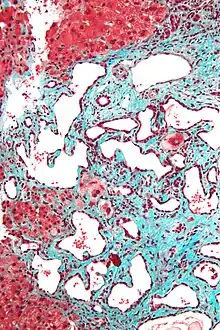

Histopathology of a bile duct hamartoma, low magnification, H&E stain, showing a well demarcated lesion.